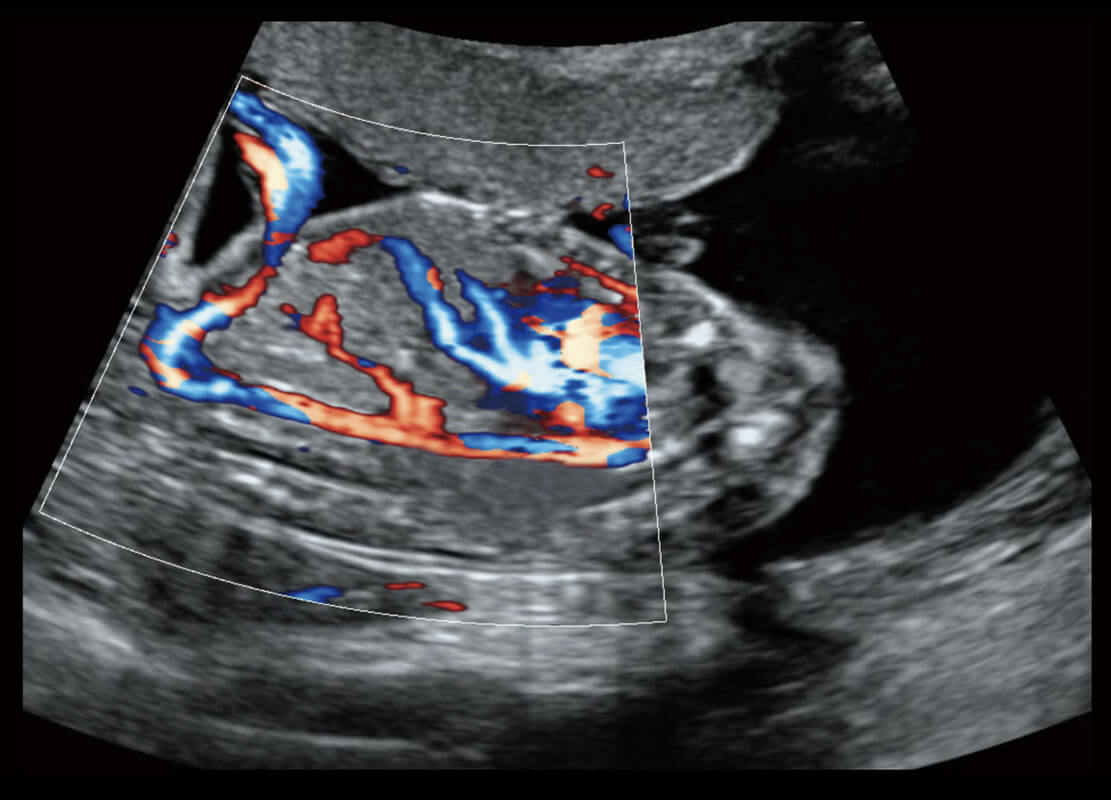

四腔心血流